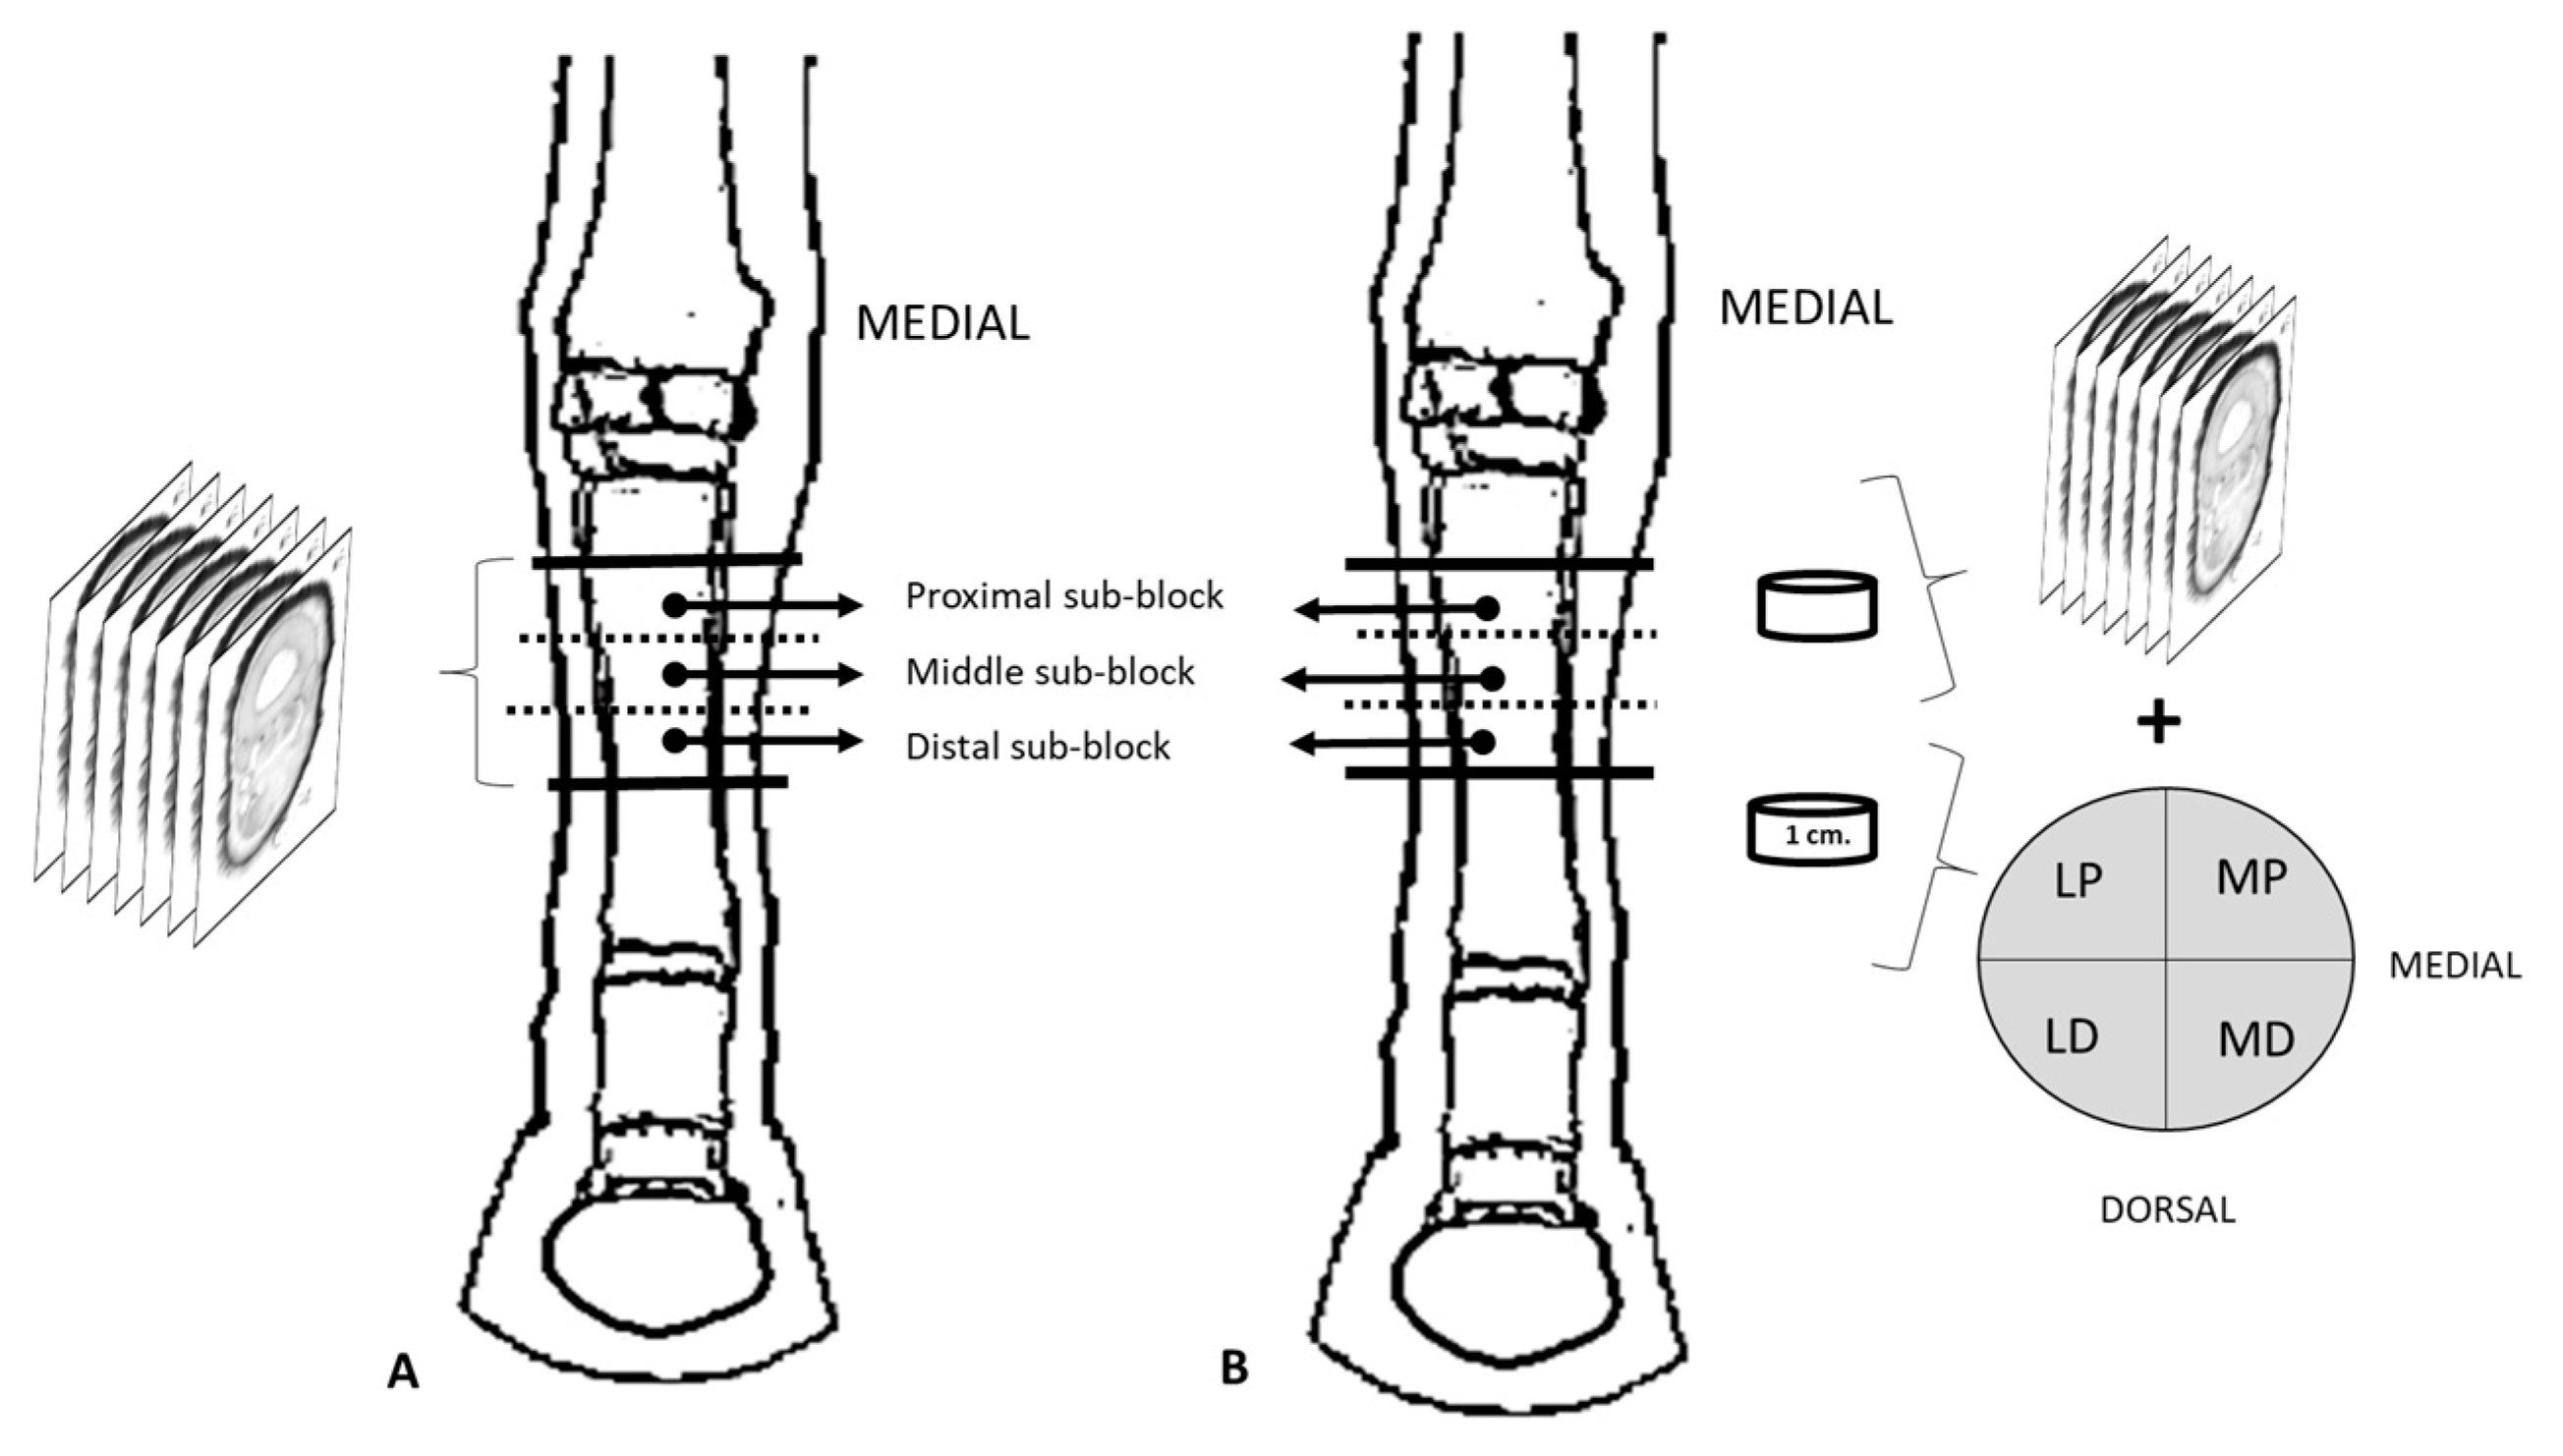

2.2. Cryosectionning

2.2.1. Plastination

2.3. Morphometry